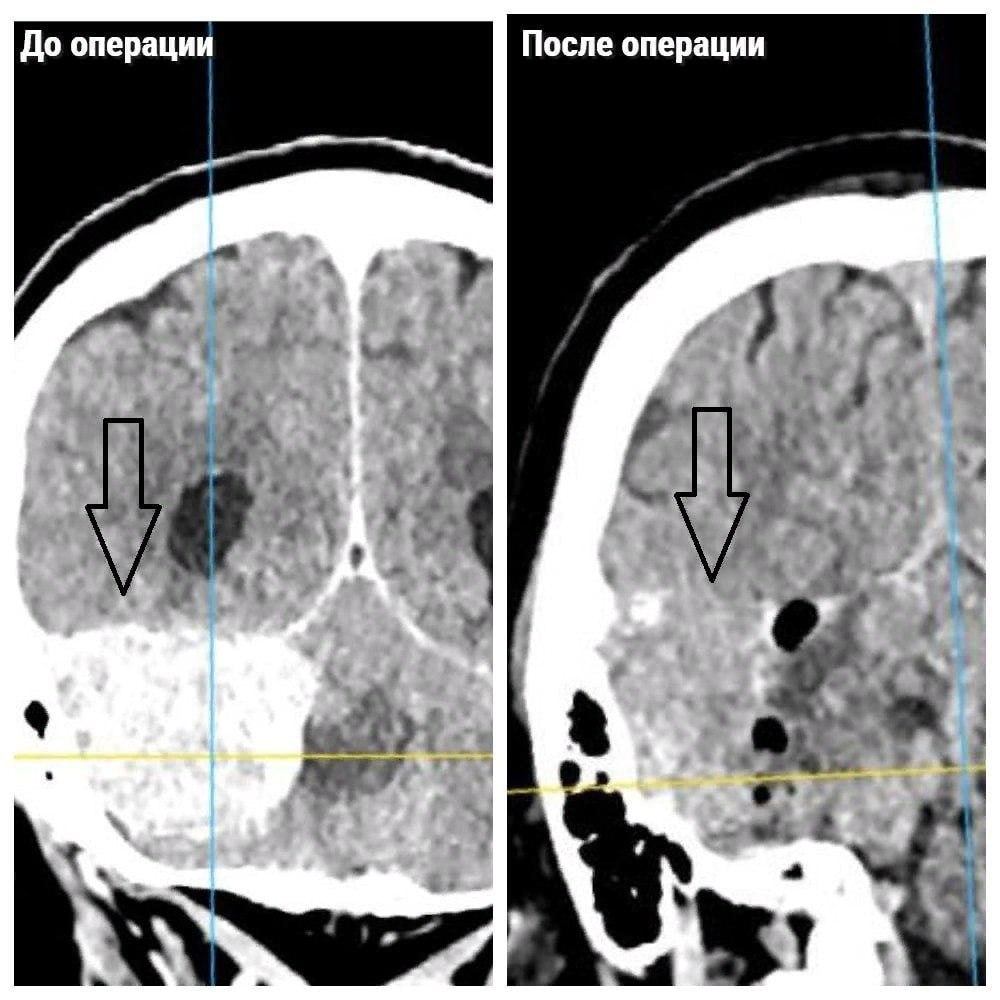

Что значит неоперабельная опухоль

Что значит неоперабельная опухоль 109 фотографий